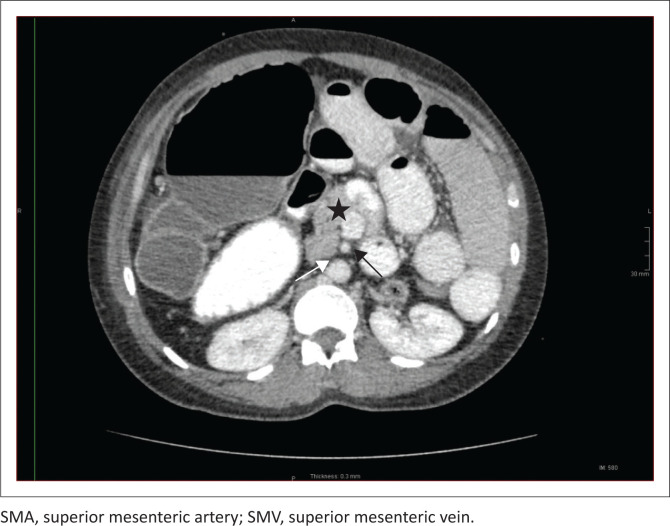

Heterotaxy syndrome, also known as situs ambiguous, is a spectrum of pathology due to loss of the normal right-to-left asymmetry of the thoraco-abdominal organs. This report describes the case of a 39-year-old female, previously well, who presented with bowel obstruction. CT showed features of left isomerism, with malrotation and volvulus.

Contribution: Heterotaxy syndrome consists of cardiac and non-cardiac manifestations. Imaging studies play a crucial role in the individualised management of the patient.